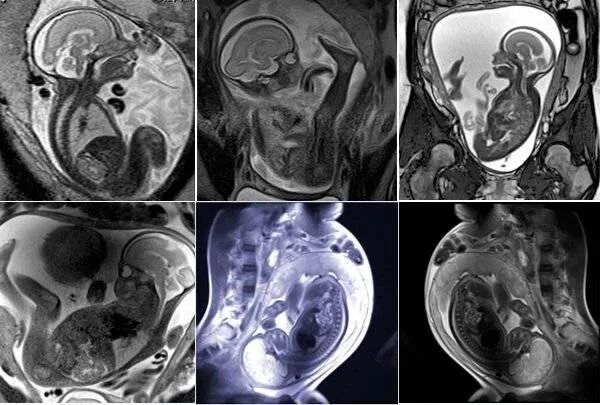

Мрт беременной